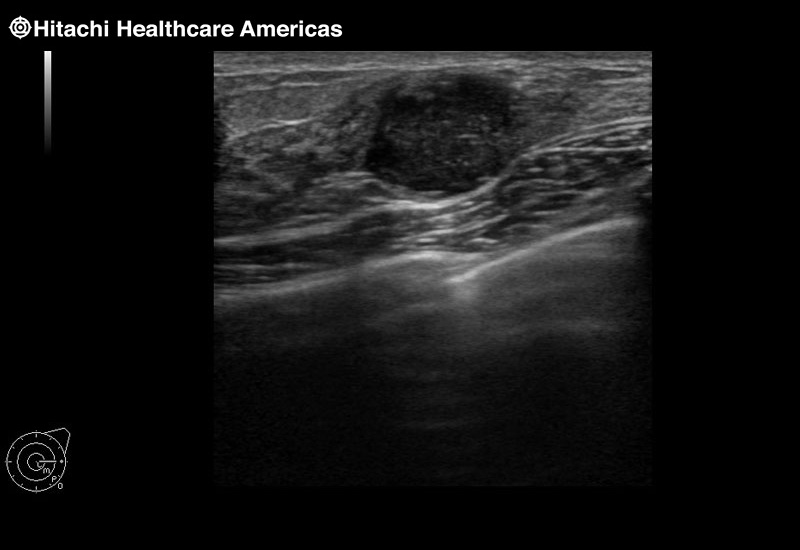

Superior guidance for all applications

Fujifilm Healthcare Americas is committed to designing tools that help surgeons navigate inside the human body and provide the necessary information to immediately make critical surgical decisions.

Fujifilm Healthcare's dedication to Surgeons provides outstanding ultrasound technology, professional support and the specialized tools necessary to best perform comprehensive real-time ultrasound imaging in Breast Surgery, General Surgery, Laparoscopic Surgery, Neurosurgery, Robotic Surgery and Surgical Oncology.

A critical function of robotic ultrasound guidance is tumor margin identification. Fujifilm's family of robotic probes all have the optimum location of the attaching mechanism that allows for full wrist articulation of the probe. The result is an increased confidence that the tumor margins have been completely identified.